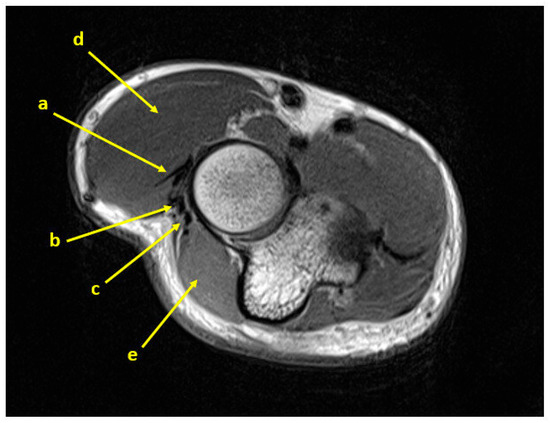

Figure 1